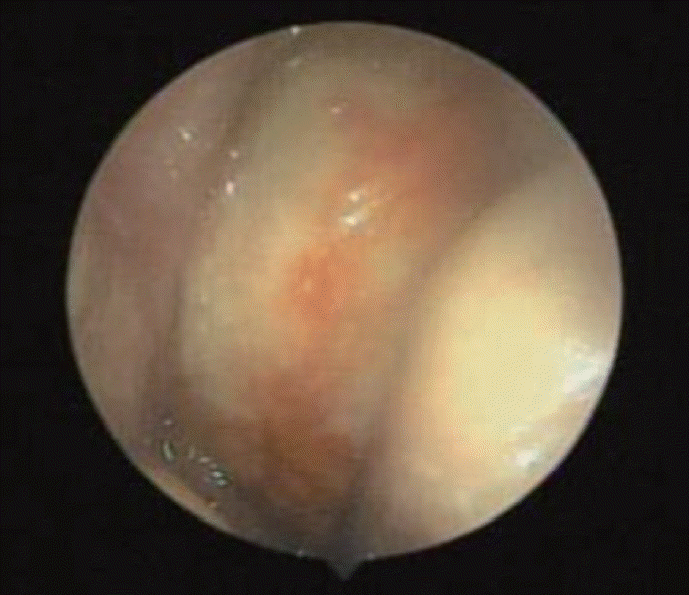

51세 남자 환자가 좌측 비강에서 발견된 종물을 주소로 본원 이비인후과에 내원하였다. 환자는 6개월 전 시작된 좌측 비출혈로 타병원을 처음 방문하였으며 우연히 좌측 비강에서 종물이 발견되어 본원으로 의뢰되었다. 환자는 지적장애 2급으로 일상적인 대화는 가능했으나 정확한 병력 청취에는 어려움이 있었다. 보호자에 의하면 환자는 비폐색과 비루를 호소하였으며 얼굴의 감각 이상이나 안구 건조증은 없었다. 신체 검사에서 피부에 밀크커피색 반점(cafe-au-lait spot)이나 국소 림프절 비대는 관찰되지 않았으며 과거력과 가족력상 특이사항은 없었다. 비내시경 검사상 광택이 나는 백색의 폴립양 종물이 좌측 비강을 가득 채우고 있었다(Fig. 1). 부비동 전산화단층촬영에서 좌측 비강에 약 7.4×5.2×5.3 cm 크기의 경계가 명확하고 조영증강이 잘되지 않은 종물이 관찰되었다. 종물 주변의 뼈는 얇아져 있었으나 골 침범의 소견은 없었으며 좌측 접형동, 사골동, 상악동에 부비동염이 의심되는 저밀도 음영이 관찰되었다(Fig. 2). 부비동 자기공명영상에서 종물은 T1 강조 영상에서 저신호 강도로 나타났으며 T1 조영증강 영상에서는 부분적으로 조영증강된 종물이 관찰되었다. 또한, T2 강조 영상에서는 종물이 고신호 강도로 나타났고 고리 모양의 구조가 고신호 강도로 나타나는 신경 다발 징후(fascicular sign)도 관찰되었다(Fig. 3). 종물에서 조직 생검을 시행하였으며 출혈은 심하지 않았다. 병리검사 결과 신경섬유종이 의심된다는 소견이 보고되었다.